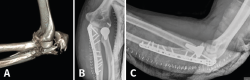

- 2A/2B: son las más frecuentes. La técnica de elección en las fracturas simples en 2 partes es un cerclaje de alambre (obenque) sobre 2 agujas de Kirschner (AK) ancladas a la cortical anterior o colocadas intramedulares. En el primer caso, tenemos riesgo de lesionar las estructuras neurovasculares volares, por lo que no deben sobresalir más de 10 mm; en el segundo caso, el riesgo de que migren proximalmente es mayor(34,35). Se pensó que con este montaje las fuerzas de tensión se transforman en fuerzas de compresión, pero varios estudios realizados no han podido demostrar este principio(36). En las conminutas 2B se recomienda fijación con placa, precisamente para evitar la excesiva comprensión de la cavidad sigmoidea que llevaría a una artrosis precoz. Se recomiendan las placas premoldeadas LCP (locking compression plate). Su efectividad y seguridad están de sobra probadas; sin embargo, al ir en una posición dorsal y ser el cúbito subcutáneo, pueden producir irritación de los tejidos blandos y con cierta frecuencia hay que retirarlas. Aun así, el índice de retirada es mucho mayor en los cerclajes, que puede llegar hasta el 90%(37,38). La alternativa es usar 2 placas laterales de bajo perfil colocadas a ambos lados de la cresta, una medial y otra lateral, que además tienen la ventaja de permitir una fijación bicortical de los fragmentos más proximales. En cualquier caso, los estudios demuestran que ambos métodos tienen buenos resultados y no existen diferencias a corto plazo. Últimamente, se están publicando modificaciones a la técnica clásica del obenque, usando una sutura trenzada de alta resistencia en lugar de alambre(39). En este caso solo tendríamos que retirar las AK y este es un proceso mucho menos invasivo (Figura 8).

Figura 8. Ejemplos de fracturas de olécranon en 2 partes (tipo 2A) fijadas con obenque (A y B) y fracturas de tipo 2B fijadas con distintos diseños de placas (C y D).